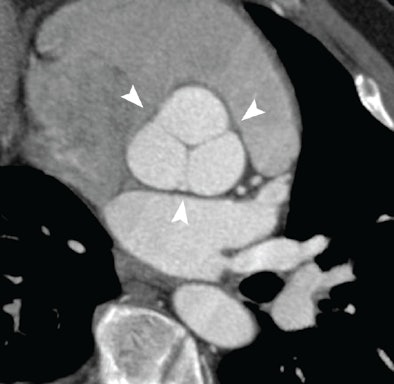

![]() |

| Normal aortic root at coronary CTA illustrating the complex cornet shape above the basal ring. Image courtesy of Dr. Geoffrey Rubin. |